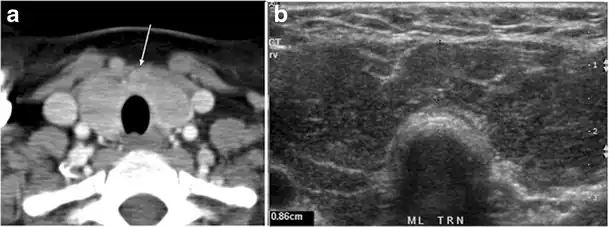

Fig. 4. A 45-year-old male patient presented with anterior mediastinal metastatic PTC lesions and occult primary on imaging. Histopathology examination of the resected thyroid gland revealed micro-foci of PTC; the largest, in the isthmus, measured 4 mm. a transverse greyscale ultrasound of the thyroid demonstrates homogeneous gland with normal echogenicity and size. No focal lesion or micro-calcifications. b Non-enhanced CT scan obtained as part of PET/CT examination shows a heterogeneous, large, relatively dense anterior mediastinal mass (white arrow) with peripheral calcification (arrowheads). Thyroid gland has normal CT appearance with no abnormal FDG uptake (not shown).[1]